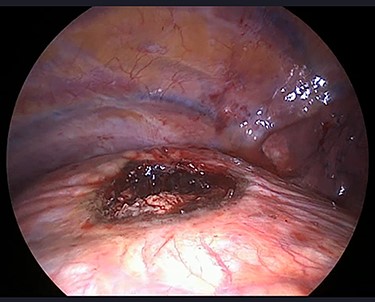

The operation was performed under general anaesthesia with the patient intubated using a double-lumen endotracheal tube. A 4 cm incision was made in the right sixth intercostal space in order to locate the mass. After the insertion of a 10 mm 30-degree thoracoscope, a rounded smooth-surfaced, broad necked mass attached to the right hemidiaphragm was visualized (Fig. 3). The decision to open the diaphragm was made. Further dissection and exploration with an energy device revealed that the mass which was bounded superiorly in the form of a pouch by the diaphragm and had arisen from the liver (Fig. 4). The mass was completely resected with HARMONIC ACE® +7 (Ethicon) after consulting with the hepatobiliary surgeon who felt there was a clear cleavage plane between the mass and liver. The exposed area of liver was covered with Floseal®(Baxter) and TachoSil®(Takeda). The diaphragmatic defect (Fig. 5) was closed in a single layer with 10 simple interrupted silk sutures (Fig. 6). The remainder of the surgery was uncomplicated, and the patient was discharged home on the second postoperative day. Subsequent histology findings reported the mass as benign (accessory) hepatic tissue (Fig. 7).